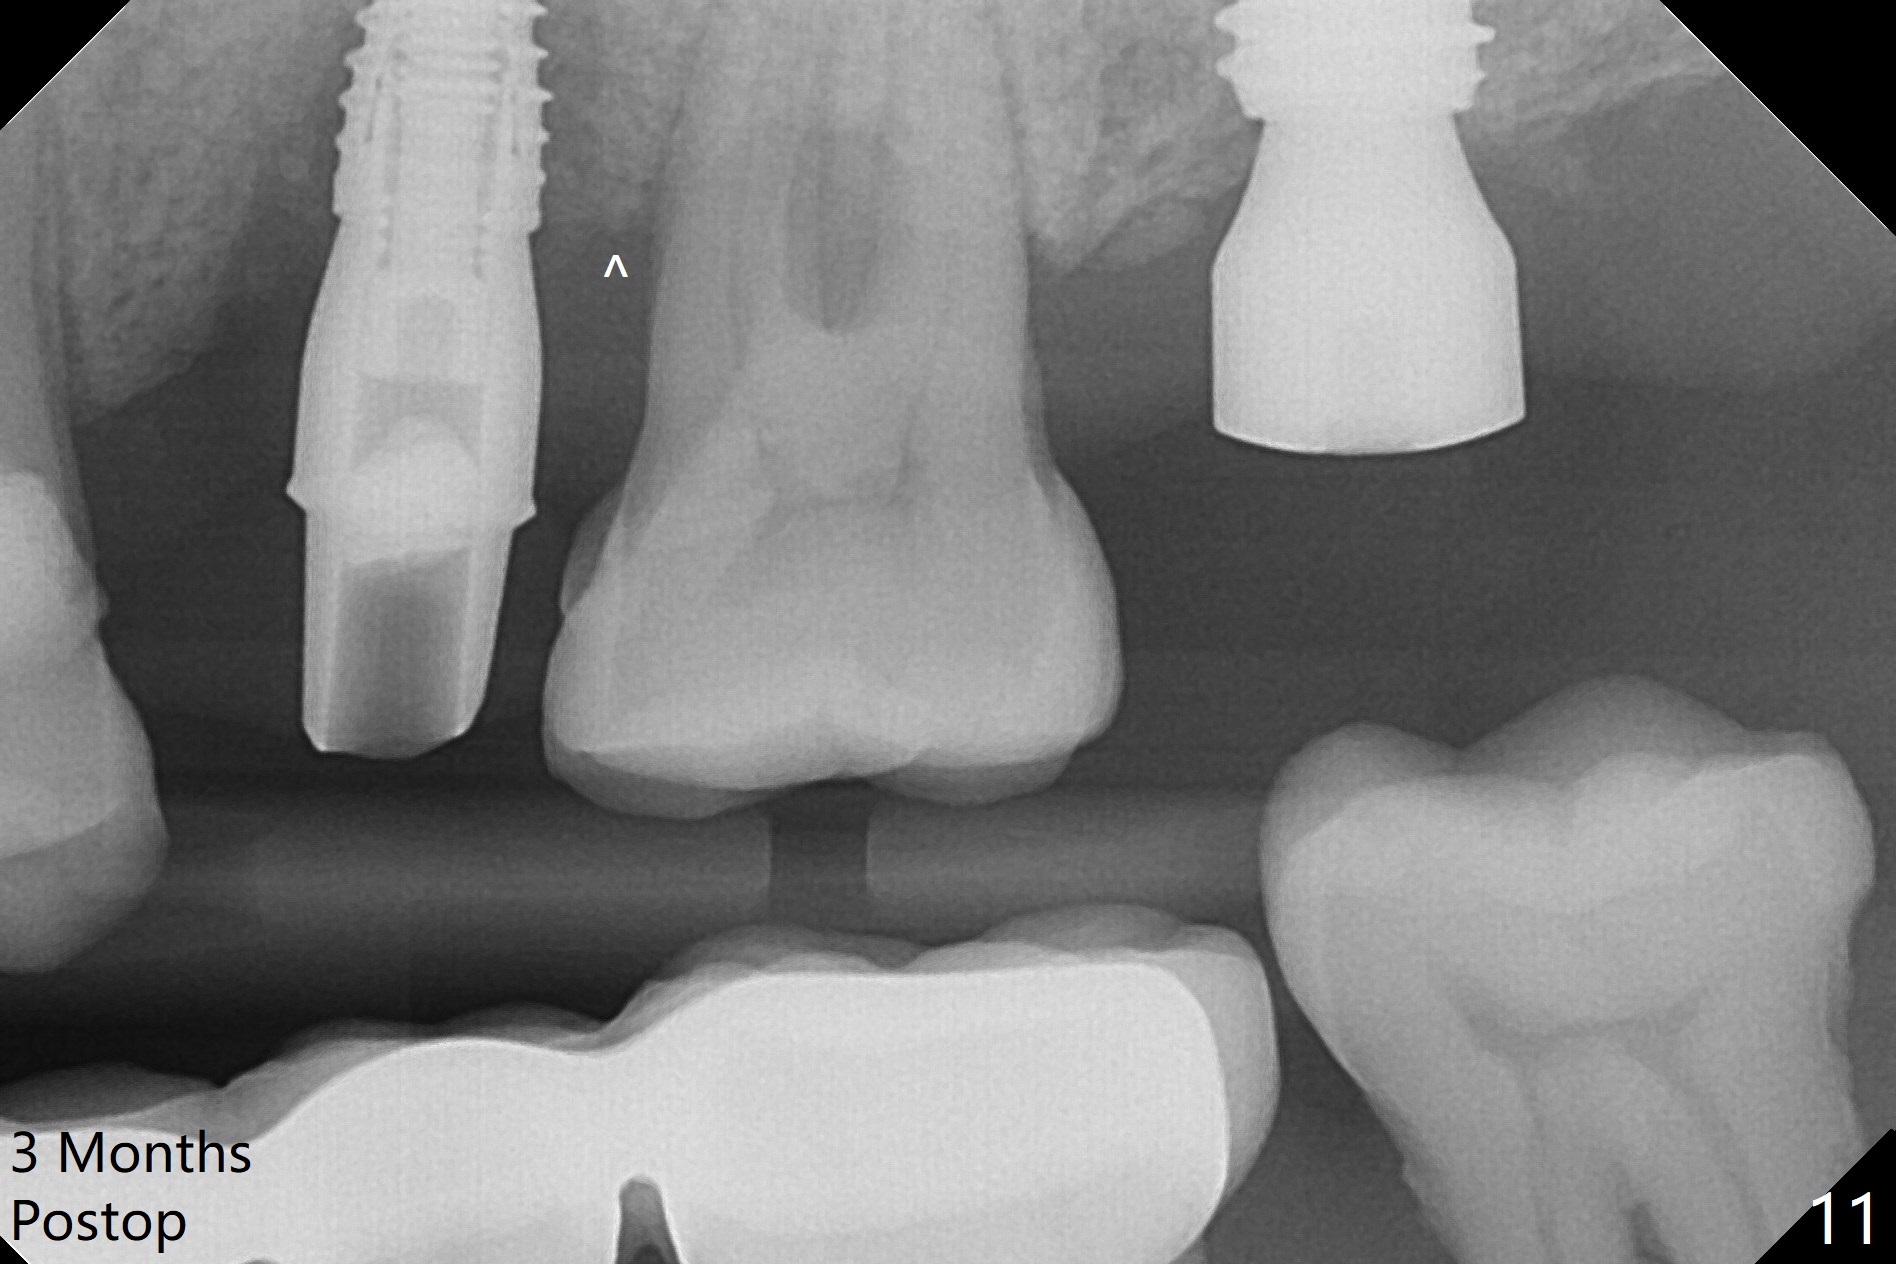

Initial osteotomy depth is 18 mm (Fig.1 green line) with 9 mm in the native bone (red line).  The bone density feels to be low.  There is at least 2 more mm bone apically (pink line).  The depth is increased by 2 mm so that when a 3.8x15 mm implant is placed, there is 10-11 mm implant/bone contact (Fig.2 red line).  There is large bony defect (Fig.3 *), which is bone grafted (Fig.4 *).  Finally a longer abutment is placed (4.5x5.5(5) in Fig.4 vs. 4.5x4(5) in Fig.2,3).  The 5 mm cuff does not look too long buccally (Fig.5) or palatally (Fig.6).   To prevent postop buccal gingival overgrowth (2), the buccal margin of an immediate provisional is subgingival (Fig.7-9 *).  Bone density between #13 and 14 appears to increase 3 months postop (Fig.10).  The implant seems to be equi-crestal (Fig.11 ^).  There seems to be more bone growth (i.e., decreasing gap) 6 months postop (Fig.12).  Impression is taken.  A crown is delivered nearly 7 months postop (08/07/2017).   While there is minimal bone loss at #13 and 15 three years and 4 months post cementation, the tooth #14 and 18 are mobile (Fig.13,14).